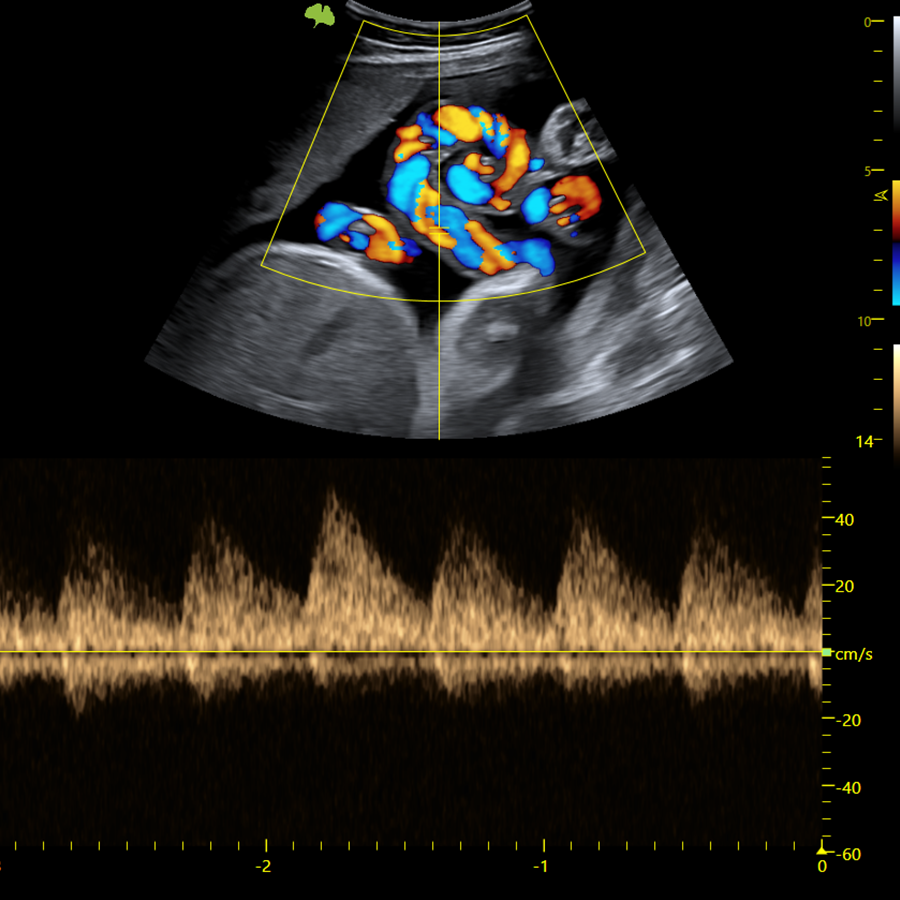

Doppler

- Modo CFM (Color)

- Modo DPI (Power)

- Modo PW (Pulsado)

- Trazo Automático de Espectro

- VFlow+

- Doppler 3D